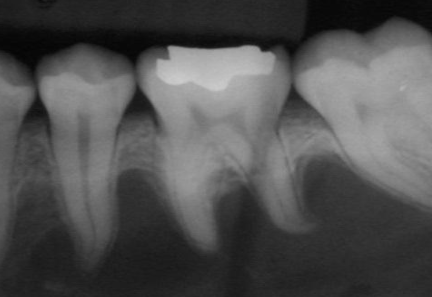

how would you describe this radiographic lesion?

a multilocular radiolucent lesion